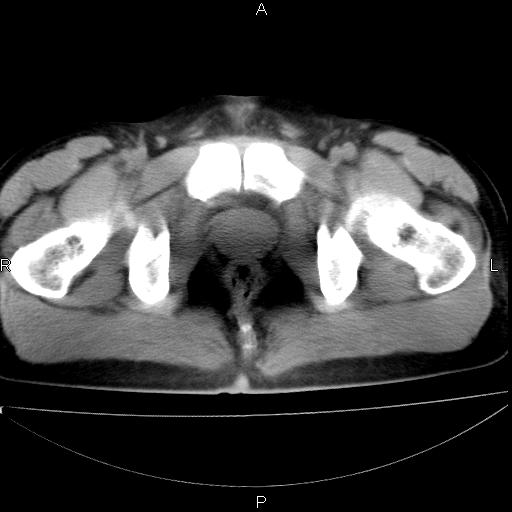

男 25岁 自述 尿频尿急,排尿困难20多天.无腰痛, b超说左肾盂轻度积水,左输尿管上端扩张.未见结石影. ct我看双侧肾盂轻度积水,双输尿管上端都扩张,大家看看能看见结石吗?

双肾轻度积水,双侧输尿管上段扩张(原因待查)。

双侧输尿管上端扩张,未见明确结石,可进一步ivp检查。

双肾盂及双输尿上段轻度积水,双输尿管未见明显结石影。

双侧输尿管上端扩张,未见明确结石,可进一步ivp检查。支持!